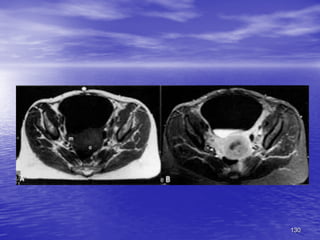

• Bàng quang

– T1W: thành BQ và nước tiểu đều có tín hiệu

thấp đồng nhất, thuốc cản quang tín hiệu cao

– T2W: thành BQ tín hiệu thấp và nước tiểu tín

hiệu cao

130

MRI of

Female

Pelvis